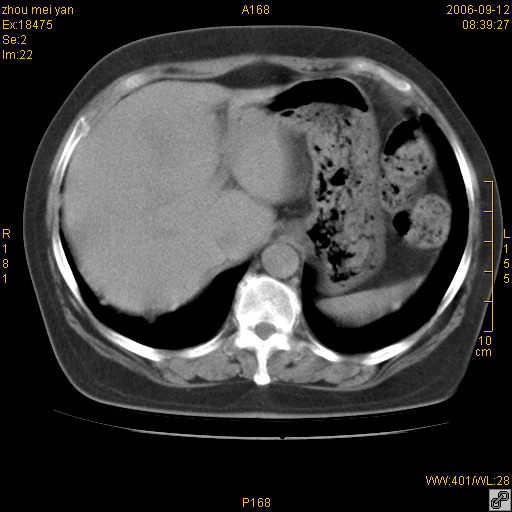

患者、女、55岁。因心率失常住院检查ct发现胸部多发结节。腹部b超肝、胆、胰、脾、肾、子宫附件未见异常。无结核病史,无粉尘接触史。请大家来会诊。谢谢!

病变位于胸膜,多发结节,边界清楚,内见小结节状钙化。其它未见异常。

感染性肉芽肿,双侧膈底胸膜见多个结节灶,内见斑点状钙化,有否疫水接触史